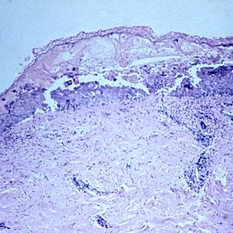

Slide 5-1 Slide 5-1Feb 20 2019 by Lancaster Course in Ophthalmology Normal lid skin from a darkly pigmented individual. Condition/keywords: normal eye